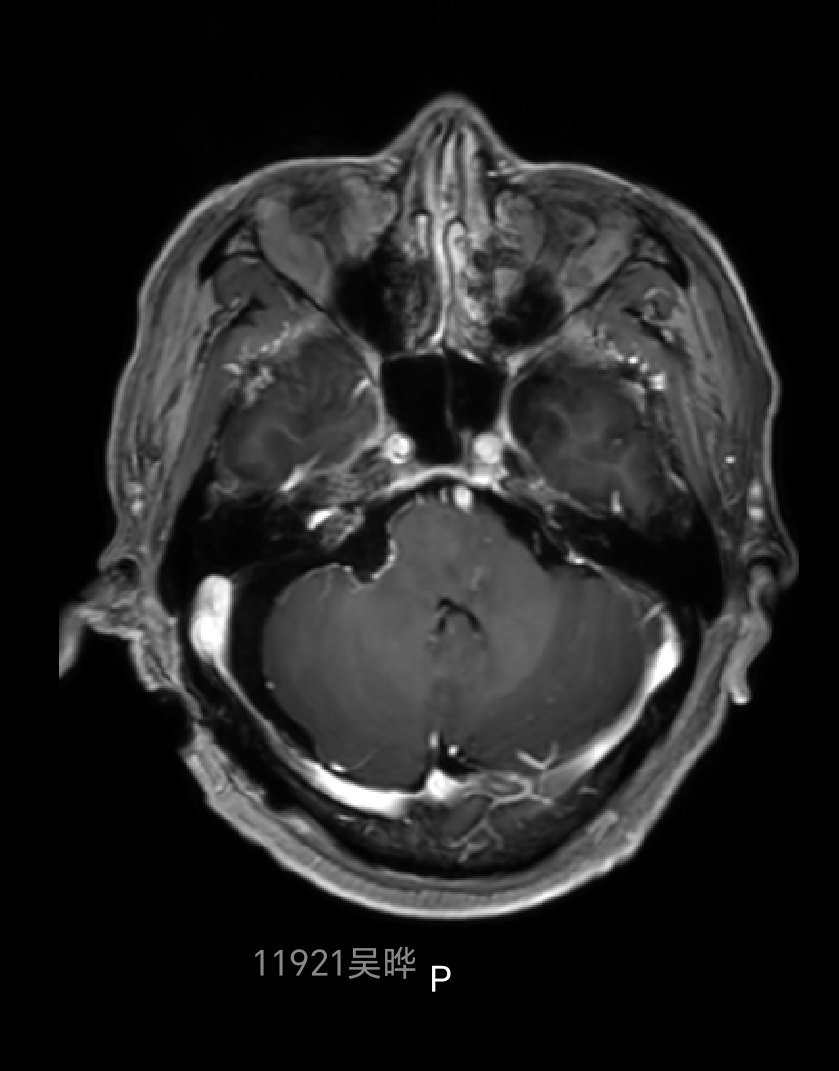

术后磁共振增强复查提示肿瘤全切,内听道内肿瘤无残留

内听道内高信号影为填塞的脂肪块